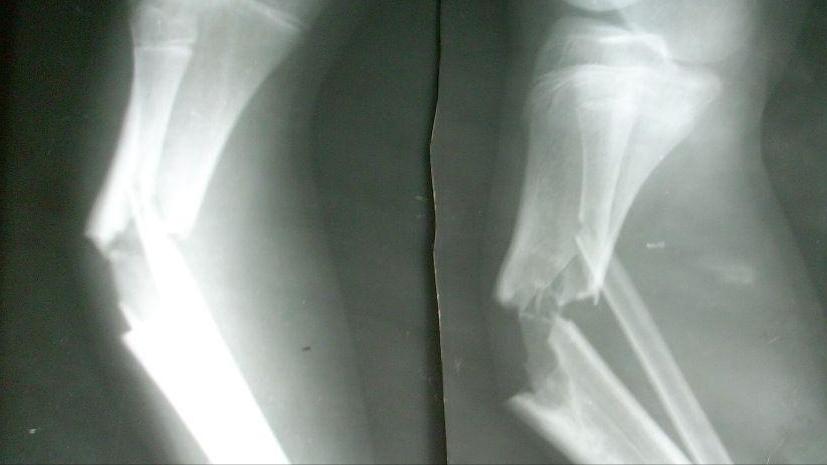

其次,脊柱肿瘤患者也会产生腰痛的症状。因为脊柱肿瘤会随着神经的运行侵害腰部肌肉,破坏骨结构、压迫神经导致腰部疼痛的症状。但是目前临床上有许多将脊柱肿瘤误诊为腰椎间盘突出的案例,患者开始都是以腰痛为主要症状就医,医生经多种治疗后,腰部疼痛仍然呈进行性加重。

最后全面检查后确诊为脊柱肿瘤。脊柱转移性肿瘤引起的腰部疼痛常呈持续性、进行性加重,并且累及多个椎体,有时剧痛难以忍受。所以,当出现腰部疼痛持续加重,就要尽快就医,明确疼痛原因,正确诊断,防止耽误病情,导致恶化。

其次,脊柱肿瘤除了会有腰痛的症状外,还会出现因肿瘤不断生长压迫脊髓及神经根的并发症,如病理性骨折、局部疼痛或麻木等,严重影响患者的生存质量。

脊柱肿瘤还可能会因为肿瘤压迫机体内局部血管,导致出现身体局部器官肿块。但是这些症状会在肿瘤切除后相应消失。